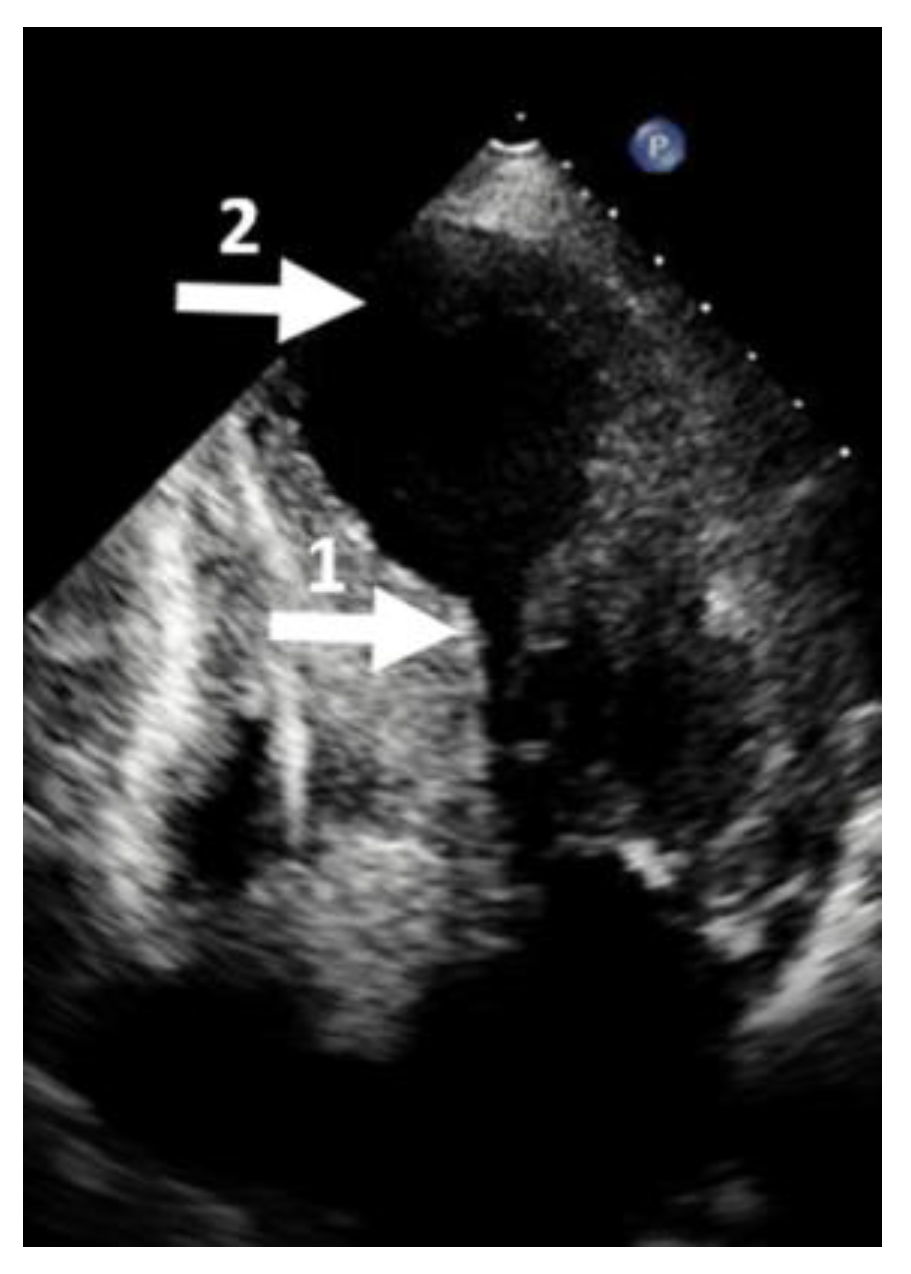

- Elsheshtawy, M.O.; Mahmoud, A.N.; Abdelghany, M.; Suen, I.H.; Sadiq, A.; Shani, J. Left ventricular aneurysms in hypertrophic cardiomyopathy with midventricular obstruction: A systematic review of literature. PACE 2018, 41, 7. [Google Scholar] [CrossRef]

- Minami, Y.; Kajimoto, K.; Terajima, Y.; Yashiro, B.; Okayama, D.; Haruki, S.; Nakajima, T.; Kawashiro, N.; Kawana, M.; Hagiwara, N. Clinical implications of midventricular obstruction in patients with hypertrophic cardiomyopathy. J. Am. Coll. Cardiol. 2011, 57, 2346–2355. [Google Scholar] [CrossRef]

- Malcolmson, J.W.; Hamshere, S.M.; Joshi, A.; O’Mahony, C.; Dhinoja, M.; Petersen, S.E.; Sekhri, N.; Mohiddin, S.A. Doppler echocardiography underestimates the prevalence and magnitude of mid-cavity obstruction in patients with symptomatic hypertrophic cardiomyopathy. Catheter. Cardiovasc. Interv. 2018, 91, 783–789. [Google Scholar] [CrossRef] [PubMed]